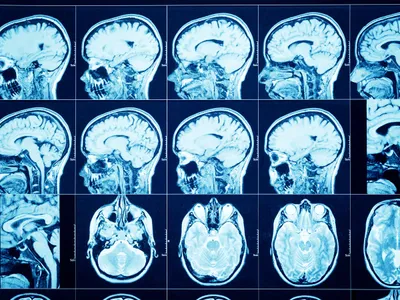

OXFORD Pacienţii COVID care au fost spitalizaţi pot prezenta simptome timp de mai multe luni

Cercetarea, condusă de oameni de ştiinţă de la Universitatea Oxford, a analizat impactul pe termen lung al COVID-19 asupra unui număr de 58 de pacienţi spitalizaţi cu această afecţiune.